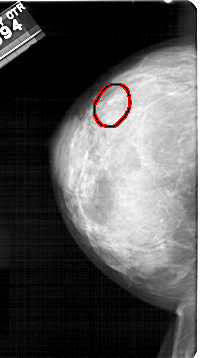

A_1326_1.LEFT_CC

LEFT_CC LINES 5356 PIXELS_PER_LINE 2986 BITS_PER_PIXEL 12 RESOLUTION 43.5 OVERLAY

FILE: A_1326_1.LEFT_CC.OVERLAY

TOTAL_ABNORMALITIES 1

ABNORMALITY 1

LESION_TYPE CALCIFICATION TYPE PLEOMORPHIC DISTRIBUTION LINEAR

ASSESSMENT 4

SUBTLETY 4

PATHOLOGY BENIGN

TOTAL_OUTLINES 1

BOUNDARY